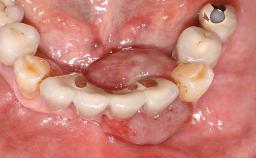

Surgical treatment of a 68-year-old female patient with a distal extension situation in the left mandible. As the CBCT analysis reveals, the bone crest anatomy in the area is not ideal and necessitates an augmentation procedure to achieve a good long-term prognosis for the planned implants and their prostheses.

After the placement of three diameter-reduced two-piece implants the bone is augmented with autologous bone chips and DBBM particles to enlarge the crest volume. The surgery is completed with the application of two membrane layers and primary wound closure.

For soft tissue management, the initial healing caps are replaced with a longer type 8 weeks after implant placement in a second intervention before prosthodontic treatment is initiated.